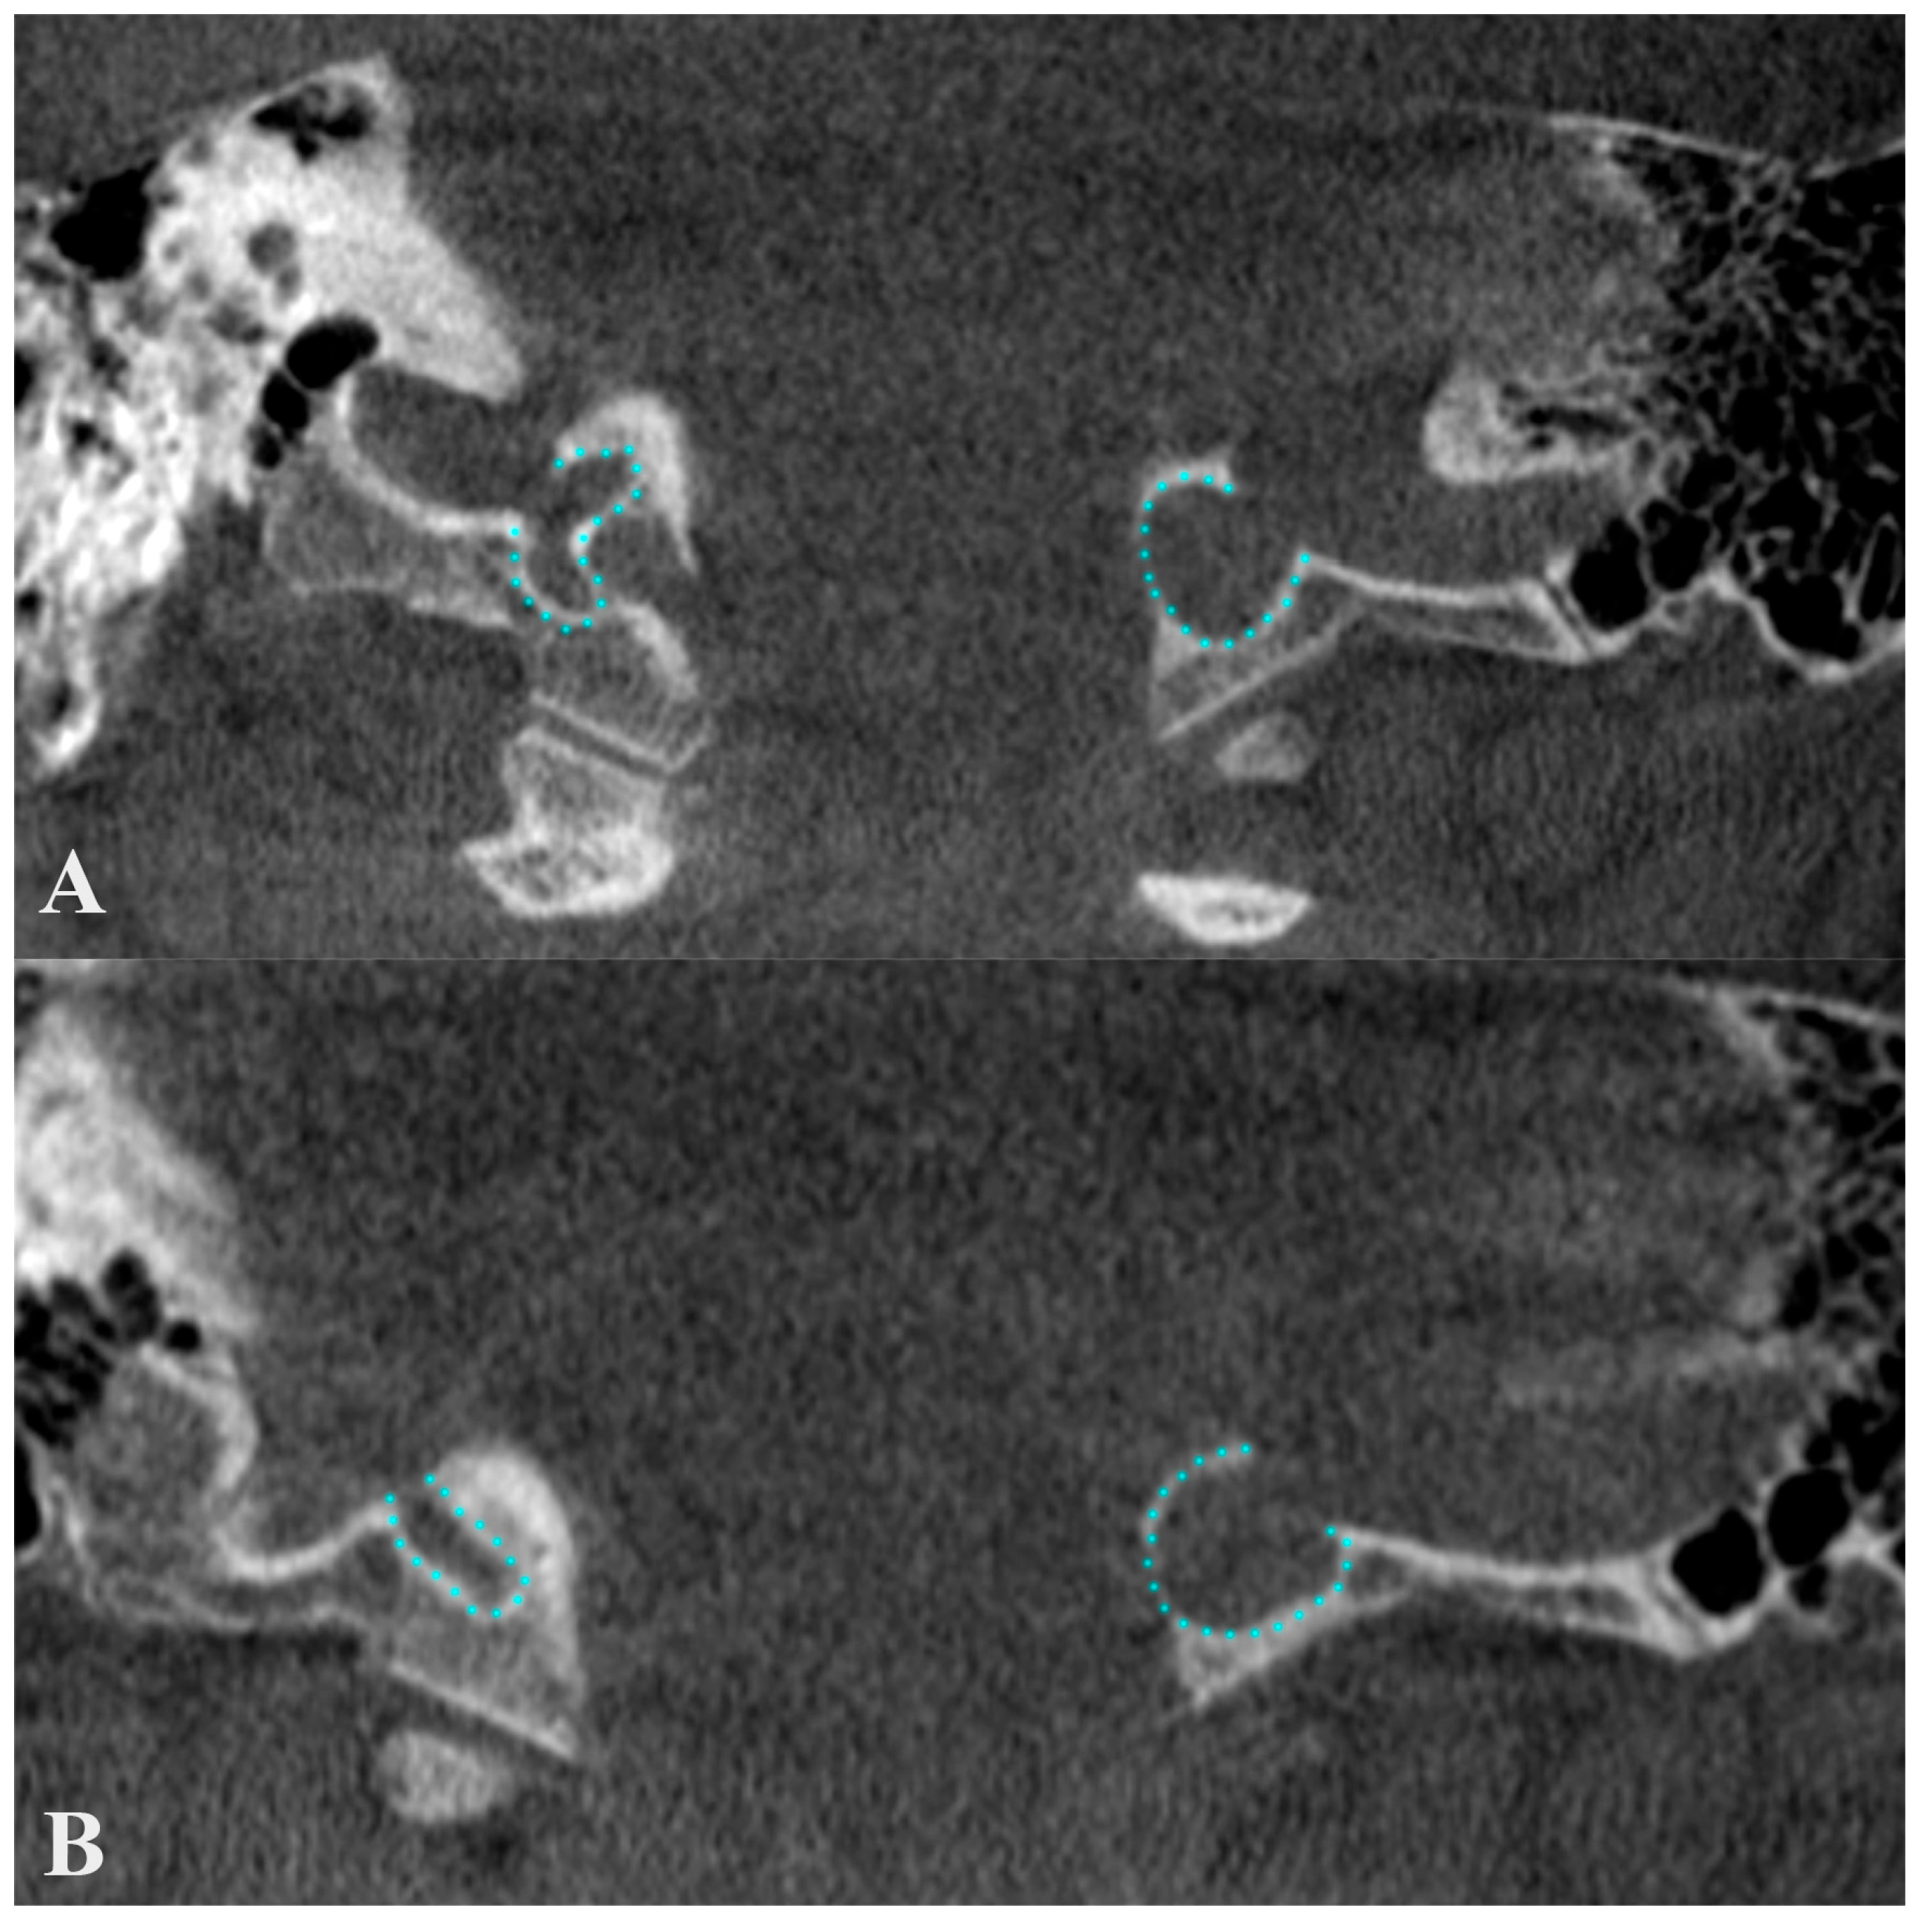

5. Dehiscent Jugular Bulb

- Hourani, R.; Carey, J.; Yousem, D.M. Dehiscence of the jugular bulb and vestibular aqueduct: Findings on 200 consecutive temporal bone computed tomography scans. J. Comput. Assist. Tomogr. 2005, 29, 657–662. [Google Scholar] [CrossRef] [PubMed]

- Koesling, S.; Kunkel, P.; Schul, T. Vascular anomalies, sutures and small canals of the temporal bone on axial CT. Eur. J. Radiol. 2005, 54, 335–343. [Google Scholar] [CrossRef]

- Huang, B.R.; Wang, C.H.; Young, Y.H. Dehiscent high jugular bulb: A pitfall in middle ear surgery. Otol. Neurotol. 2006, 27, 923–927. [Google Scholar] [CrossRef]

- Harnsberger, R.; Hudgens, P.; Wiggins, R.; Davidson, C. Dehiscent jugular bulb. In Diagnostic Imaging: Head and Neck, 3rd ed.; Amirsys/Elsevier Saunders: Salt Lake City, UT, USA, 2006; pp. 18–22. [Google Scholar]

- van Die, A.; de Groot, J.A.; Zonneveld, F.W.; Vaandrager, J.M.; Beck, F.J. Dehiscence of the jugular bulb in Crouzon’s disease. Laryngoscope 1995, 105, 432–434, discussion 434–435. [Google Scholar] [CrossRef]

- Tomura, N.; Sashi, R.; Kobayashi, M.; Hirano, H.; Hashimoto, M.; Watarai, J. Normal variations of the temporal bone on high-resolution CT: Their incidence and clinical significance. Clin. Radiol. 1995, 50, 144–148. [Google Scholar] [CrossRef]